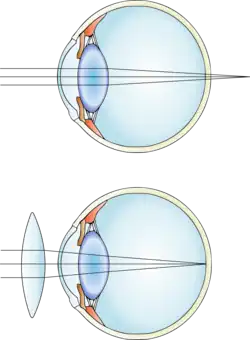

Этот дефект заключается в том, что из-за аномалии рефракции в покое аккомодации изображение фокусируется не на сетчатке глаза, а за сетчаткой. В молодом возрасте, при не слишком высокой дальнозоркости, обычно удаётся сфокусировать изображение на сетчатке с помощью напряжения аккомодации. Дальнозоркие люди часто испытывают головные боли при выполнении работы вблизи.

Дальнозоркость может быть исправлена при помощи как очков, так и контактных линз, чтобы изменить направление лучей света в глазу. Больные зачастую вынуждены носить очки или контактные линзы всё время или только для близи (читая, работая на компьютере или выполняя другую близкую работу).